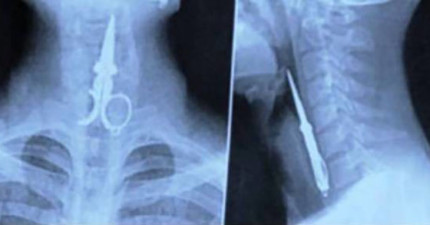

18個連醫生都不相信會在人體裡發現的奇怪物品。

February 12, 2015

世界